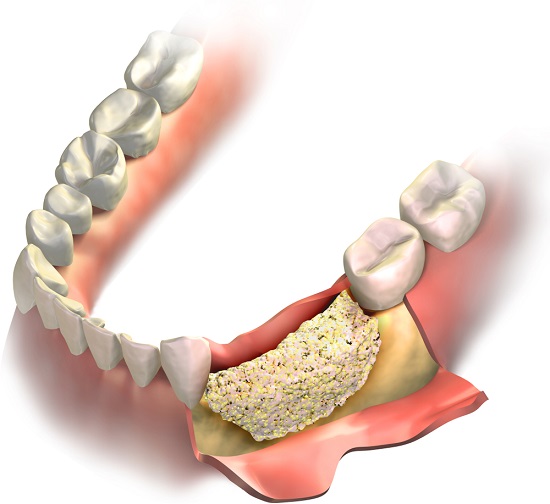

Înainte de a se reconstrui adiția de os, specialistul ține cont de trăsăturile naturale ale maxilarului pacientului. Pentru acest lucru sunt folosite mai multe tehnici de adiție osoasă. Foarte important: unele dintre acestea se pot aplica imediat, adică poți beneficia de zâmbetul tău natural chiar în aceeași zi în care s-a făcut intervenția. Altele necesită intervenții repetate de-a lungul câtorva luni.

Foto: By AMoukhin /Shutterstock

„De exemplu, dacă unui pacient îi cade un singur dinte, osul începe să se resoarbă în zona respectivă din cauza lipsei de stimul.Ceea ce îl menținea înainte de cădere era rădăcina lui. Cu cât trece mai mult timp, cu atât osul mandibular se resoarbe și mai mult. Iar dacă au trecut mulți ani, implantul nu mai poate fi inserat direct, pentru că acum nivelul osului este scăzut. Dacă implantul dentar ar fi plasat direct în os, acesta ar fi sub linia celorlalți dinți, ceea ce ar face ca mestecatul să fie dificil. Ca să nu mai vorbim, că nici din punct de vedere estetic nu ar arăta prea bine. Dacă am plasa implantul la nivelul celorlalți dinți, rădăcina metalică ar fi extrem de vizibilă. În acest caz, nu doar că este inestetic, ci și instabil, deoarece implantul este înșurubat prea puțin. Nici cazul în care am folosi punte sau coroană dentară nu este optim, deoarece acestea nu vor avea o bază de fixare și va rămâne un gol între ele și os. Astfel că, singura soluție pentru ridicarea și reconstrucția osului resorbit este adiția de os. ”, exemplifică dr. Lorelei Nassar, stomatolog cu o experiență de peste 28 de ani în implantologie și chirurgie oro-maxilo facială.

Mai departe, cu ajutorul unui instrument, doctorul umple complet golul cu un substituent de os dentar, iar chirurgul implantolog izolează lucrarea de adiție cu ajutorul unui alt instrument stomatologic. Finalul operației de adiție osoasă constă în coaserea zonei cu fire de sutură, pacientul este trimis acasă și de acum începe procesul de vindecare. După un timp, grefa osoasă va fi absorbită și integrată complet în maxilar, iar zona vindecată, astfel că se poate insera implantul dentar. Acesta va arăta și se va comporta la fel ca un dinte natural, deoarece a fost reconstruit osul care îl susține.